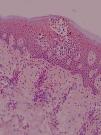

Expresión de moléculas de adhesión en biopsias cutáneasAntígeno ICAM-3 (CD50) (fig. 1)En la piel sana se observó marcaje de células dendríticas epidérmicas (células de Langerhans) y en la dermis expresión en células de estirpe linfomonocitaria, representando un porcentaje variable del total de células (media 15,25%). Las células endoteliales fueron completamente negativas y en los folículos se apreció expresión en forma de células dendríticas.

En el resto de procesos, el marcaje para CD50 mostró en epidermis marcaje intenso de células dendríticas así como del infiltrado linfocitario epidermotropo. La expresión en células de estirpe linfomonocitaria de los infiltrados dérmicos representaron un porcentaje elevado del total de células. Se apreció expresión en forma de células dendríticas distribuidas aisladamente en la dermis y en células situadas en áreas perivasculares. Además, la intensidad de expresión de ICAM-3 en los linfocitos que infiltran la piel fue uniforme en las diferentes dermatosis.

Se valoró de manera independiente el número de linfocitos intraepidérmicos ICAM-3 positivos por campo lineal epidémico a 400× y el porcentaje del infiltrado dérmico ICAM-3 positivo. La tabla 3 presenta las medias y desviación estándar en la observación de la tinción en células de estirpe linfocitaria y la tabla 4 los valores de p<0,05 en el análisis comparativo entre los diferentes grupos.

Se observaron diferencias estadísticamente significativas entre el número de linfocitos intraepidérmicos (p=0,005) y el porcentaje de células dérmicas (p=0,027) en los diferentes grupos de pacientes. Estas diferencias se presentaban entre todos y cada uno de los grupos patológicos considerados LCCT inicial, LCCT avanzado, enfermedades inflamatorias y pre-LCCT con el grupo sano. En el caso de los linfocitos epidérmicos ICAM-3 positivos también se observaron diferencias entre los grupos LCCT inicial y las enfermedades inflamatorias y entre este último y el grupo pre-LCCT. Los valores más elevados correspondieron al grupo LCCT inicial seguido por el avanzado y del pre-LCCT. El porcentaje medio de células del infiltrado dérmico ICAM-3+ fue mayor en el grupo de las enfermedades inflamatorias.